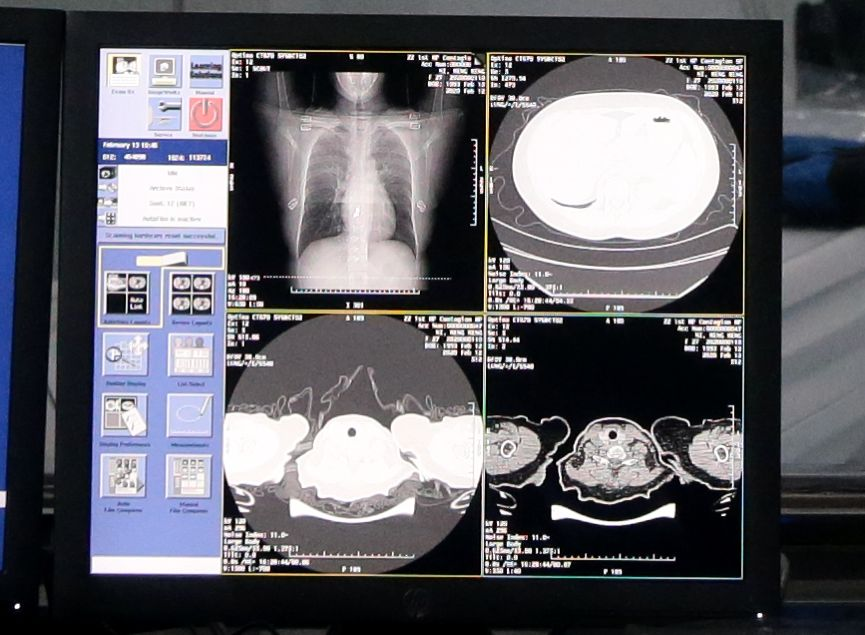

AI 判读 CT 影像: 2 月 15 日,达摩院联合阿里云,针对新冠肺炎临床诊断研发了一套全新 AI 诊断技术,可对新冠疑似案例 CT 影像做出判读,分析结果准确率达到 96%,时间不超过 20 秒,大幅提升诊断效率。

AI 自动识别新冠肺炎病例 CT 胸片